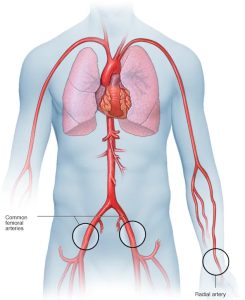

A coronary angiogram is part of a general group of heart tests and treatments called cardiac catheterization. Cardiac catheterization uses one or more thin, flexible tubes, called catheters. The tubes are placed within the major blood vessels of the body and the heart. The test requires a small cut in the skin. During a coronary angiogram, a treatment called angioplasty and stenting can be done to open any blocked arteries.

The doctor makes a small cut, called an incision, to reach an artery. This cut may be made in the leg or wrist. A thin, flexible tube called a catheter is placed in the artery and guided to the heart. You shouldn’t feel it moving through your body.

Once the catheter is in the correct position, dye flows through the tube into the heart’s blood vessels. X-ray images are taken to see how the dye moves. These images are called angiograms. If the dye doesn’t move through a blood vessel, it could mean the area is blocked or narrowed.